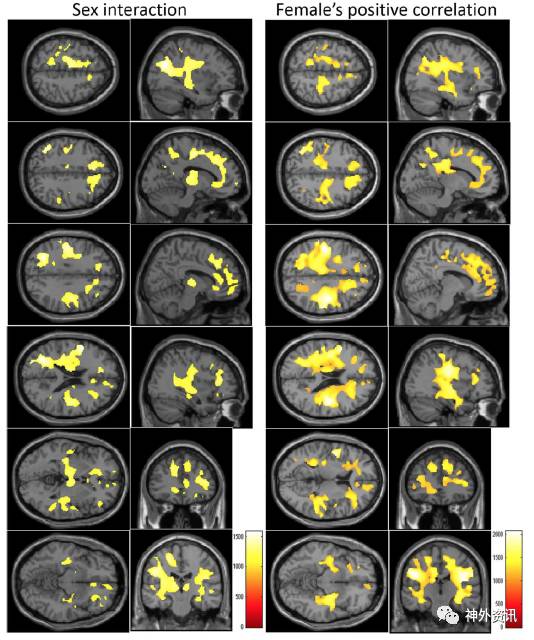

结果显示,在新皮质下的大片白质区发现rWMV与CMDT得分之间呈显著的正相关性,而且在女性人群中尤为明显(图1)。而该CMDT关系在扩散张量成像的各向异性分析中没有观察到。

图1. 左图显示,CMDT和性别对rWMV的相互影响效应区域;右图显示,CMDT与rWMV呈正相关显著差异的区域。